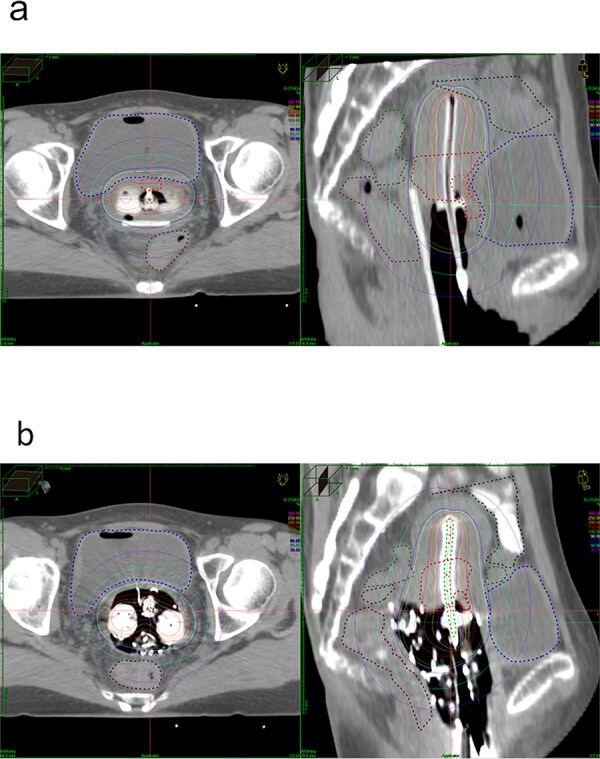

本研究旨在比较和验证使用直肠牵引器(RR)和纱布填塞(GP)的腔内近距离放射治疗(ICBT)在同一患者中的直肠和膀胱剂量。本研究共纳入37例使用RR和GP治疗宫颈癌的ICBT患者。将直肠和膀胱剂量和体积数据与同一患者的RR和GP治疗进行比较,并检查混杂因素。当比较RR和GP时,直肠D2cc的中位数和四分位数范围分别为RR组2.8 (2.5-3.7)Gy和GP组3.2 (2.7-3.8)Gy。RR组膀胱D2cc中位数为4.9 (4.5-6.3)Gy, GP组为4.8 (3.9-5.4)Gy。Wilcoxon符号秩检验显示直肠剂量显著低于RR (P = 0.02),而膀胱剂量显著高于RR (P = 0.02)

This study aimed to compare and verify the rectal and bladder doses of intracavitary brachytherapy (ICBT) using both rectal retractor (RR) and gauze packing (GP) in the same patients. A total of 37 patients who underwent ICBT using RR and GP for cervical cancer were included in this study. Rectal and bladder dose and volume data were compared with the RR and GP treatments in the same patients and the confounding factors were examined. When comparing RR and GP, the median and interquartile ranges for rectal D2cc were 2.8 (2.5-3.7) Gy with RR and 3.2 (2.7-3.8) Gy with GP. The median bladder D2cc was 4.9 (4.5-6.3) Gy with RR and 4.8 (3.9-5.4) Gy with GP. The Wilcoxon signed-rank test revealed that rectal doses were significantly lower with RR (P = 0.02), whereas bladder doses were significantly higher with RR (P < 0.001). Analysis of the correlation between the number of gauze pieces and the difference in rectal D2cc between GP and RR using Pearson's distribution revealed no significant correlation (R = -0.20, P = 0.22), as well as bladder D2cc between GP and RR also revealed no significant correlation (R = -0.20, P = 0.22). The number of gauze pieces did not necessarily correlate with a reduction in the rectal and bladder dose. In conclusion, rectal D2cc was lower with RR in image-guided brachytherapy for cervical cancer, whereas bladder D2cc was higher with RR than with GP.